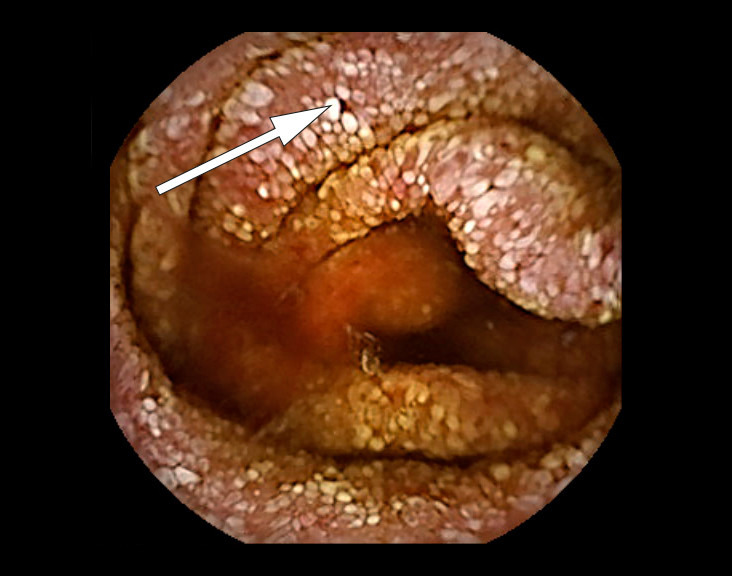

Konstellasjonen av migrerende leddsmerter og synovitter over flere år uten utvikling av radiologiske artrittforandringer, kombinert med intermitterende diaré og proteintapende enteropati gjorde at vi mistenkte Whipples sykdom, en sjelden infeksjonssykdom forårsaket av den grampositive bakterien Tropheryma whipplei. Pasienten ble henvist til gastroskopi og kapselendoskopi av tynntarm som viste betydelig inflammasjon med erosjoner, hemoragiske slimhinner og diffus lymfangiektasi (fig 2) (fig 3). Duodenalbiopsier viste breddeøkte totter og akkumulering av skummakrofager med periodisk syre-Schiff (PAS) diastasepositive granulære inklusjoner i cytoplasma (fig 4) (fig 5). Både de makroskopiske og histopatologiske funnene var godt forenlig med Whipples sykdom. PCR utført etter DNA-ekstraksjon fra parafininnstøpt tarmbiopsi var positiv for T. whipplei for to separate målgener (varmesjokkprotein og 16S rRNA). Sekvensering av 16S rDNA PCR-produktet bekreftet T. whipplei. Pasientens ikke-destruktive seronegative artritt, diaré, malabsorpsjon og utmattelse ble antatt å representere manifestasjoner av Whipples sykdom. Iskemiske slag og lungeembolier er beskrevet hos pasienter med Whipples sykdom, og sykdommen representerte en plausibel årsak til pasientens hittil uforklarlige trombosetendens (1),( 2).

Klassisk Whipples sykdom diagnostiseres på bakgrunn av øvre endoskopi, duodenalbiopsier og PCR-undersøkelse. Gastroskopi kan vise ødematøse slimhinner med erosjoner og lymfangiektasi. Lymfangiektasien skyldes akkumulering av makrofager i lymfekarene, med resulterende lymfestase. Allikevel er det viktig å være klar over at de fleste pasientene har makroskopisk normal tynntarmsslimhinne, så biopsier anbefales selv ved upåfallende gastroskopi (5). Multiple biopsier øker sensitiviteten (6). Kapselendoskopi av tynntarm kan brukes for å kartlegge sykdomsutbredelsen. Mikroskopering av duodenalbiopsi viser akkumulering av skummakrofager med PAS-positive intracellulære inklusjoner. Det PAS-diastase-positive materialet svarer til bakteriekapselen som inneholder mykopolysakkarider. Andre årsaker til PAS-positive makrofagansamlinger i tynntarm er blant annet mykobakterieinfeksjon, avleiringssykdommer og langerhanscelle-histiocytose. Disse differensialdiagnosene kan avkreftes med tilleggsundersøkelser.